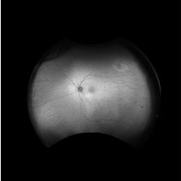

Branch retinal artery occlusion Branch retinal artery occlusionJan 24 2023 by Rayna Marshall Widefield fundus autofluorescence image of a 54-year-old female with an asymptomatic chronic branch retinal artery occlusion in the left eye. Hyper-autofluorescent embolus present at proximal inferior arcade, hypo-autoflorescence temporally corresponding to hyper-pigmentation. Vision was 20/20. Photographer: Drew H. Scoles, MD, PhD, University of Pennsylvania Condition/keywords: branch retinal artery occlusion (BRAO), BRAO, embolus